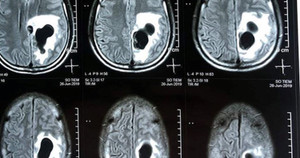

Thấy hành động của chồng vô lý, người vợ linh cảm có điều gì đó bất ổn nên đưa anh đến bệnh viện khám. Bác sĩ kết luận chồng chị bị rối loạn hành vi, nhân cách, biểu hiện sự ghen tuông cực kỳ bất thường.

Theo TS. BS Trần Thị Hồng Thu, Phó Giám đốc Bệnh viện Tâm thần ban ngày Mai Hương (Hà Nội), bệnh nhân Thành là một trong những trường hợp bị chứng hoang tưởng ghen tuông. Thành tự nghĩ ra những tình huống chồng hoặc vợ ngoại tình trong khi gia đình vẫn êm ấm, hạnh phúc.

Hoang tưởng ghen tuông là dạng rối loạn nội dung tư duy, nhẹ là ám ảnh về việc vợ có nhân tình, phản bội mình, nặng là hoang tưởng những tình huống kỳ quái, không có thực. Chứng hoang tưởng ghen tuông đôi khi kéo dài rất lâu, từ năm này qua năm khác mà người thân không phát hiện đó là bệnh.